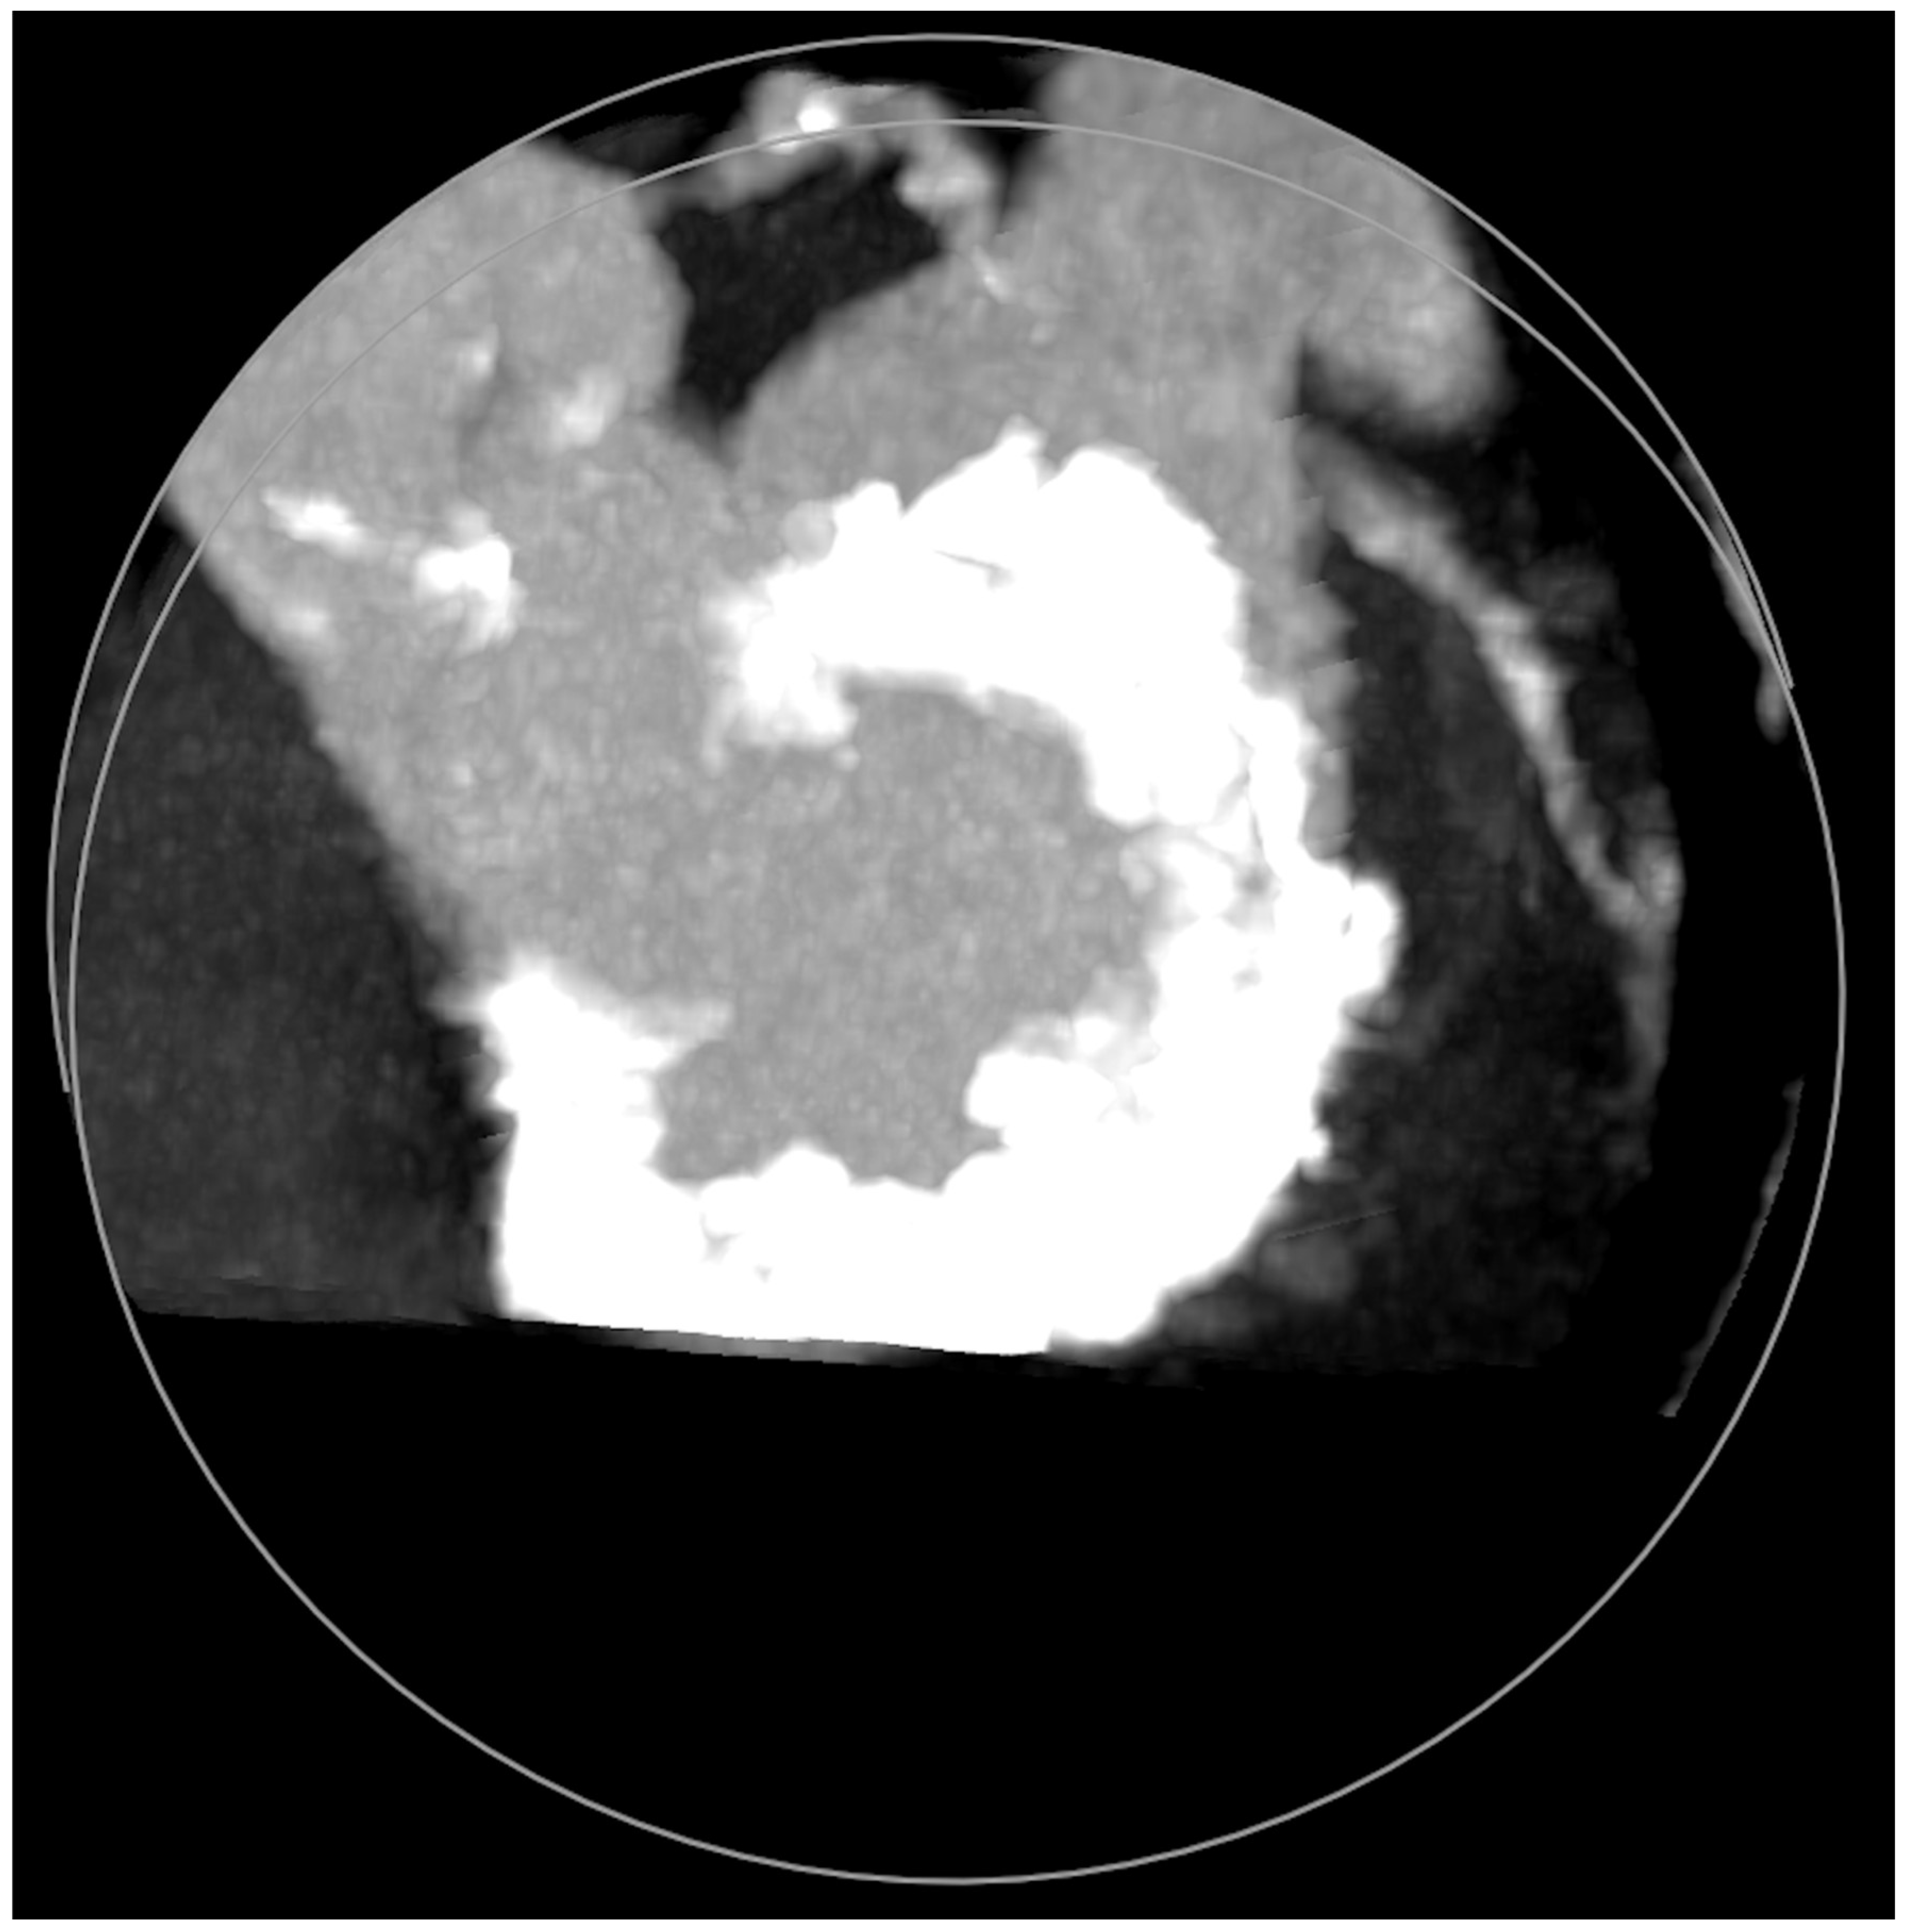

MAC consist of circumferential calcific depositions around the mitral valve, especially in the posterior aspect (Figure 5), but sometimes involve the whole mitral fibrotic annulus. It is considered a chronic degenerative condition, although it may be associated with rheumatic mitral disease. It is important to note that MAC has been clearly associated with a worse prognosis due to coronary artery disease and myocardial ischemia, ventricular arrhythmias, cardiovascular events (including mortality), and mitral and aortic valve dysfunctions [11]. MAC more frequently cause MR than MS [12]. Cardiac imaging tools, which are important before mitral lithotripsy, become critical when planning a ViMAC procedure. Apart from transthoracic echocardiography, TEE, and fluoroscopy, cardiac computed tomography (CT) with contrast has emerged as the cornerstone imaging modality since it allows the quantification of the density, severity, and extension of MAC and its relationship to other cardiac structures [13].

Figure 5.

Mitral annular calcifications (MAC), which allow grading of the valvular calcium burden and extension.

Five observational studies have been published since 2017 exploring the safety and efficacy of ViMAC, all of them with aortic balloon-expandable bioprosthesis in prohibitive surgical risk patients [17,18,19,20,21]. Their designs and main results are summarized in Table 1. To note, the ViMAC procedure shows worse results in terms of technical success and short- and mid-term outcomes than those of ViV and ViR. Indeed, ViMAC is the most challenging percutaneous scenario of all types of TMVR. Mortality at the one-year follow-up is high (around 50%), underscoring the importance of patient selection and of performing these interventions in experienced centers. When comparing the three approaches of TMVR for ViMAC, transatrial appears to have the best results, with one-year rates of mortality at 35% (25% in the latest series) [16,22,23], compared to those of transapical (57%) and transseptal (63%), and higher technical success rates (89% vs. 71% and 65%, respectively). The most important adverse event is the obstruction of the LVOT, with a hazard ratio for mortality of 2.87 (95% confidence interval 1.66–4.96) [19], so this must always be anticipated by a preprocedural CT. An area below 170 mm2 in the LVOT once the valve is implanted (“neo-LVOT”) is highly predictive of this complication (Figure 6) [13]. Other important CT parameters include the angle between the aorta and the LV axis (Figure 7), mitral annulus dimensions (Figure 8), and 2D- or 3D-derived virtual reconstructions (Figure 6).

Figure 6.

“Virtual” valve reconstruction (blue line) and neo-left ventricular outflow tract measurements.